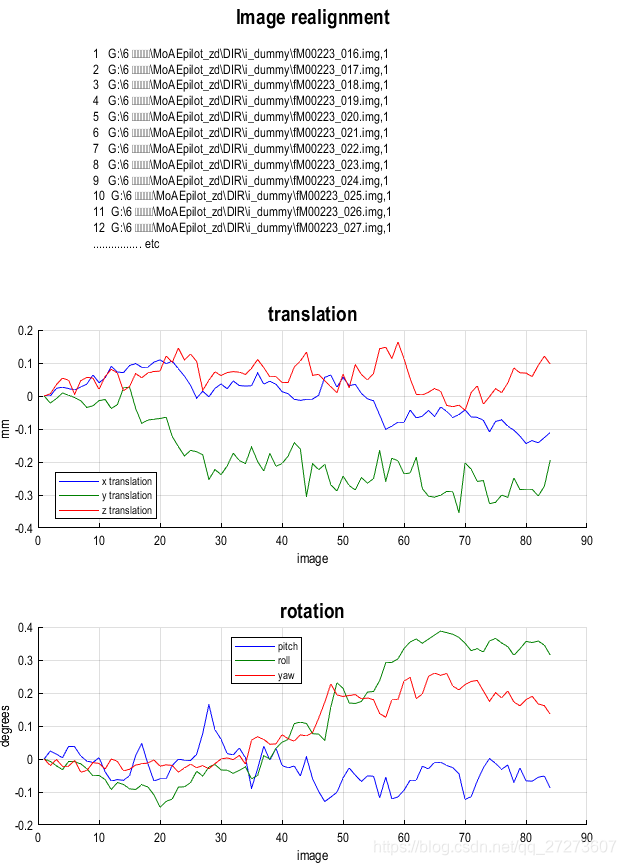

运行完程序后,matlab窗口出现‘Done ‘Realign: Estimate & Reslice’’。然后得到两个结果,记录受试者的头动情况。